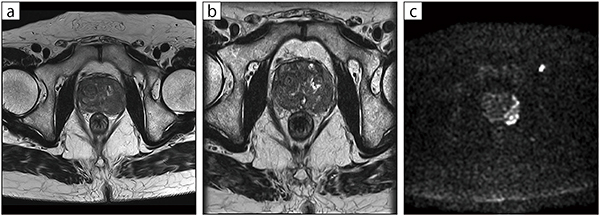

ECHELON Smart Plusの画像について,加藤部長はREALISE Plusによるデノイズ効果を高く評価しており,特に3D撮像での高画質化が著しいという。「当院では泌尿器科の検査も多く行っていますが,前立腺がんや膀胱がんの浸潤の有無などが鮮明に確認できます。また,近隣の開業医からの紹介検査で直腸の撮像なども行っていますが,ECHELON Smart Plusでは3Dシーケンスの画質が向上しており,大変有用だと感じています」と話す。

■症例3:前立腺がん壁外浸潤疑い

79歳,男性。3mmのT2Axiでは壁構造との境界が不明瞭であったが(a),0.75mmの3D撮像にて境界の正確な情報が取得できた(b)。

a:2D,T2WI,AX,スライス厚:3mm,scantime3:09,TR/TE:4600/130

b:3D,T2WI,AX,スライス厚:0.75mm,scantime4:43,TR/TE:2000/118.2

c:DWI,AX,スライス厚:3mm,scantime3:29,TR/TE:6329/94.1